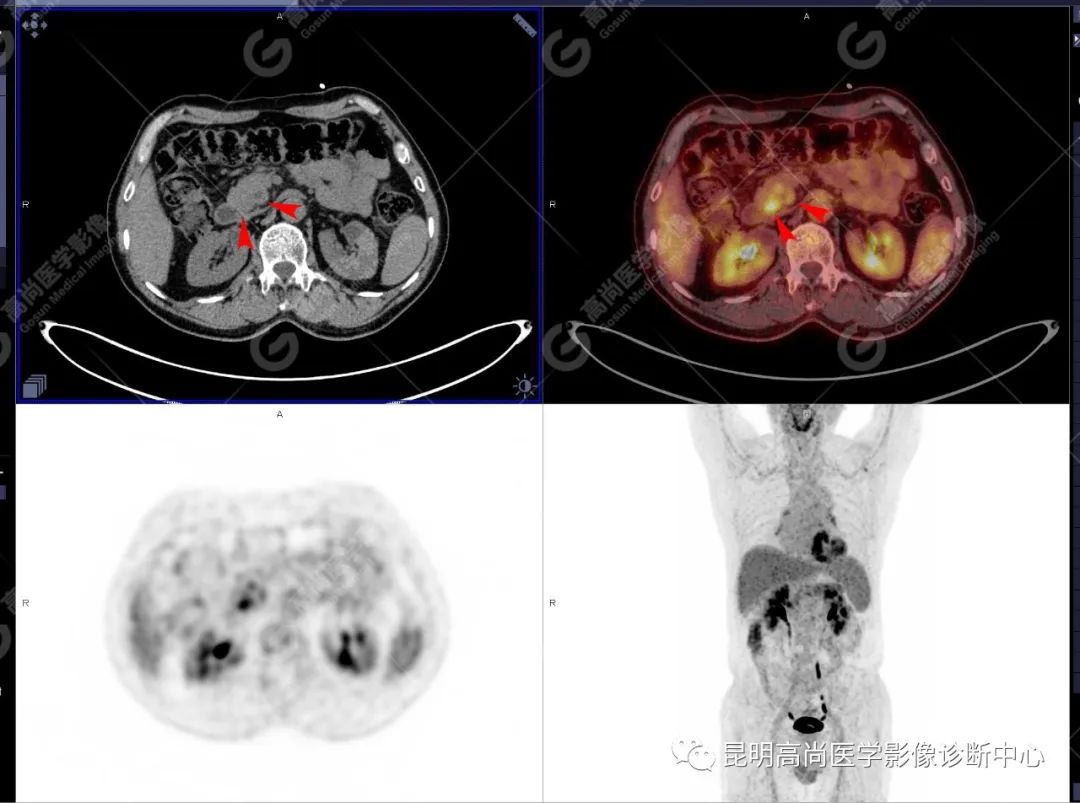

十二指肠壶腹区等密度结节影伴糖代谢持续增高,多考虑恶性病变(壶腹癌),继发主胰管扩张及慢性胰腺炎表现;腹膜后多发淋巴结显示,糖代谢不同程度增高,不除外转移。

(4)18F-FDG PET/CT

在诊断胰腺癌方面具有较高的敏感性,其敏感性可达 85%~90%,特异性可达 55.6%~94%;尤其在鉴别良恶性的囊性肿瘤时,其准确率可达到 94%~95%;PET/CT 是胰腺癌的主要检查手段,它比常规 CT 和 MRI 更具优势,可早期发现远处转移灶;同时可以作为一个独立的、用于预测胰腺癌生存和无进展生存的独立的指标,即 SUV,代谢肿瘤体积,即 MTV。